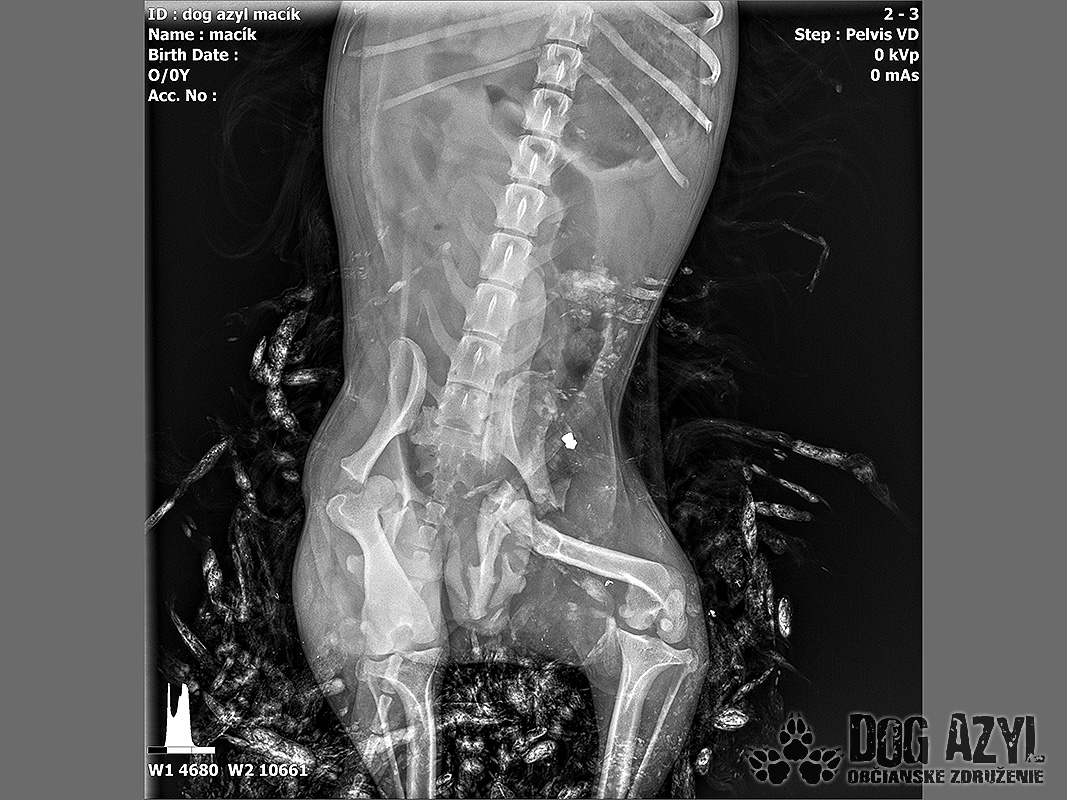

Vianoce nám klopú na dvere a mali by to byť sviatky radosti a pokoja. No u nás nebudú a pre malého Jamesa už vôbec nie. Malého Jamesa sme prijali s mnohonásobnými fraktúrami panvy. Presnejšie, s obojstrannou iliosakrálnou luxáciou/fraktúrou, viacnásobnou fraktúrou panvy, vrátane fraktúry kranialneho acetabula obojstranne. Áno, znie to hrozivo a keď si pozriete snímky z RTG, bude to ešte hrozivejšie (ďalšie snímky ešte doplníme).

Čakali ho teda štyri, veľmi náročné ortopedické operácie, takže sa musel trocha posilniť. Do starostlivosti si ho vzala MVDr. Panyi Terzieva a 17.11. mohol absolvovať prvú operáciu. V "prvom kole" krpec zvládal anestézu tak dobre, že sa rovno mohli spojiť dve operácie a tak sa celá ľavá strana dala do poriadku. Zostal samozrejme naďalej hospitalizovaný. Ďalší zákrok sa naplánoval na 20.11. a našťastie opäť všetko prebehlo hladko, a zoperovala sa celá pravá strana(nechceme sa dlho rozpisovať, prikladáme lekársku správu). James bol prepustený 24.11. ako chodiaci pacient a bez problémov ovládal aj vylučovanie! Je to priam zázrak, za ktorý opäť vďačíme MVDr. Vatolíkovi a jeho teamu.